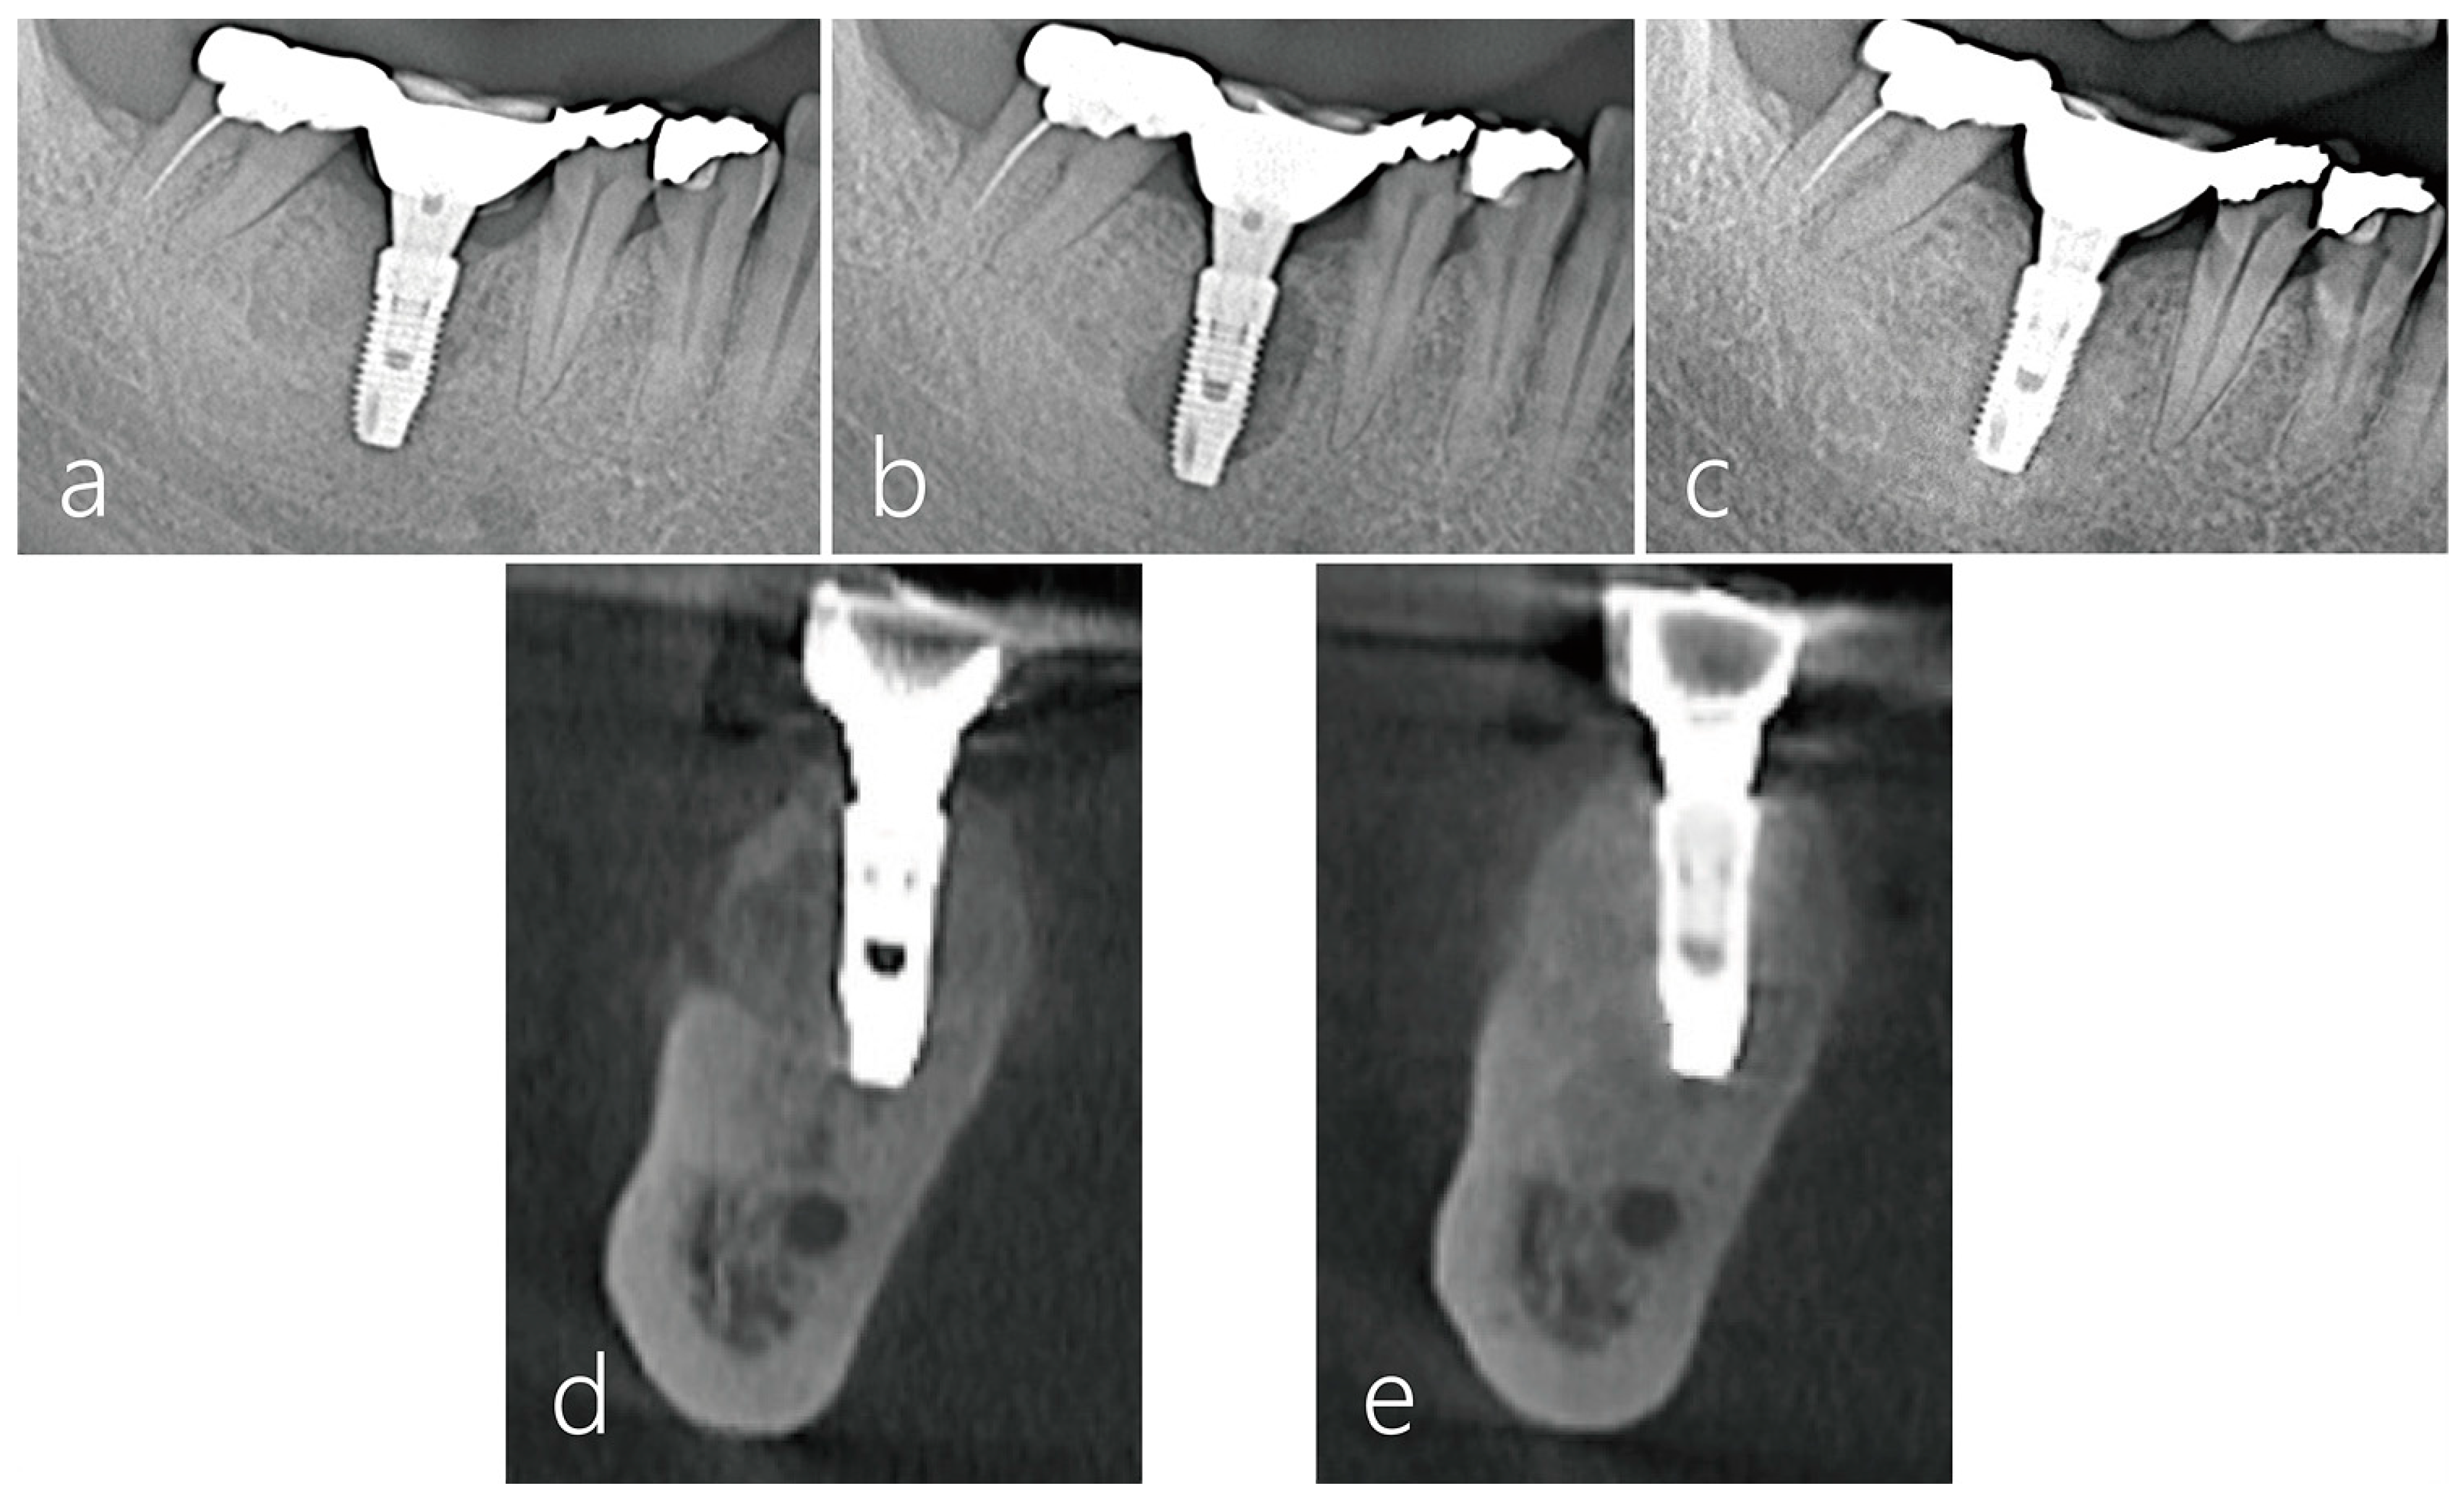

2.6. Radiographic Evaluation